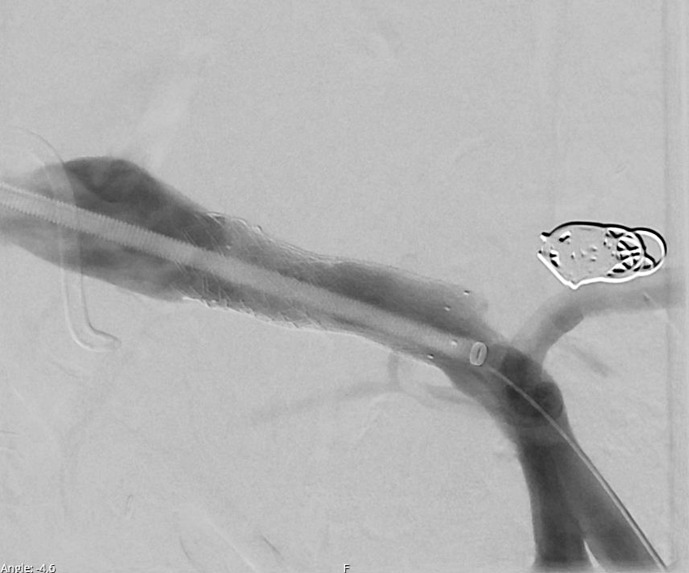

简介:门静脉假性动脉瘤是胰十二指肠切除术后一种罕见但可能危及生命的并发症。我们在此报告这一严重并发症的成功微创治疗:一位 68 岁的男性患者曾在另一家医院接受胰十二指肠切除术和门静脉楔形切除术,因持续胆汁渗漏和间歇性出血来到我科就诊。腹部计算机断层扫描显示,胰空肠造口周围有大量积液,肝总动脉闭塞,门静脉假性动脉瘤。治疗采用了微创方法,包括放置血管内门静脉支架和通过开裂的肝空肠造口进行经皮经肝胆道引流(PTBD)。随后在胰周积液处放置经皮胰尾,以充分引流。放置支架后,抗生素的使用时间共计 6 周。在随后的几周内,PTBD 可以被内化,辫子也可以被移除,之后患者就可以出院了。在门诊就诊时,通过 PTBD 注射造影剂证实没有胆汁渗漏,之后引流管即可拔除:本文介绍了为数不多的已发表的胰十二指肠切除术后门静脉假性动脉瘤病例,并强调了微创血管内支架和 PTBD 置入术在处理这种罕见且可能致命的并发症中的重要作用。

Case presentation: A 68-year-old male patient who had undergone pancreatoduodenectomy with portal vein wedge resection at another facility presented to our department due to persistent bile leakage and intermittent bleeding. Abdominal computed tomography scanning demonstrated a large fluid collection surrounding the pancreatojejunostomy, with an occlusion of the common hepatic artery as well as a portal vein pseudoaneurysm. Treatment was performed by means of a minimally invasive approach, including endovascular portal vein stent placement and percutaneous transhepatic biliary drainage (PTBD) through the dehiscent hepaticojejunostomy. This was followed by the placement of a percutaneous pigtail in the peripancreatic fluid collection for adequate drainage. Antibiotics were administered for a total duration of 6 weeks following stent placement. In the subsequent weeks, the PTBD could be internalized and the pigtail removed, after which patient was discharged. During outpatient visits, a contrast injection through the PTBD confirmed the absence of bile leakage, after which the drain could be removed.